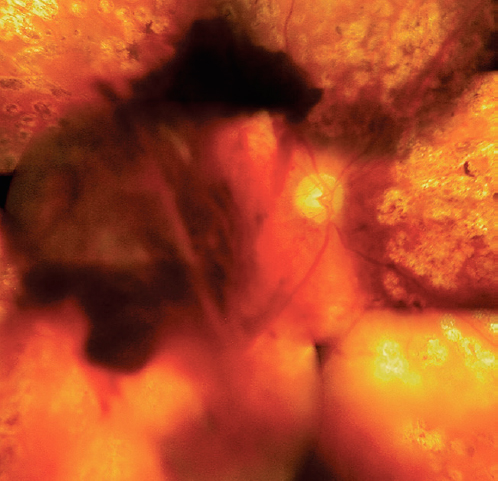

Во всех 55 глазах имел место сопутствующий гемофтальм (рис. 3). Его длительность варьировала от 2 нед. до 2 лет, в среднем — 6 мес. На 13 глазах он был тотальным, в 42 глазах — в виде взвеси эритроцитов в витреальной полости, преретинальных и витреальных геморрагий.

Рис. 3. Пациент В, 30 лет. Правый глаз. Гемофтальм, глиоз, тракционная отслойка сетчатки. Сахарный диабет 1-го типа на протяжении 20 лет. HbA1С 9%, нефропатия.